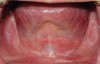

Palatal and vestibular depth influences the available ridge height present (Figure 2). When a standard denture or overdenture is on the arch, the act of chewing encompasses both a vertical and horizontal motion that place lateral forces on the prosthesis. The denture/overdenture flanges are in contact with the remaining ridge. The higher the ridge, the more lateral bracing occurs during chewing and the less displacement of the prosthesis from the arch laterally (Figure 3). Yet, when a low ridge height is available—either due to a shallow palate or vestibule or combination of these—the ridge has minimal effect at bracing against lateral displacement (Figure 4). This increases lateral loading and the shear loads placed on freestanding implants. When these anatomic factors are noted during the initial examination, the patient should be made aware of the need for splinting the implants with a bar to assist in distributing the loading forces over the entire arch and to shield the individual implants from shear loading. Patients who have shallow vestibules but adequate vestibular depth have two options regarding the prosthetics (Figure 5). If freestanding implants are to be used, maintaining palatal coverage may be needed. This may not require full palatal coverage, and depending on the anatomy, eliminating the posterior one-third may be possible while maintaining the anterior two-thirds to aid in stability via a hard stop on the non-movable anterior palate when the patient occludes. As stated earlier, lateral loads are not handled as well as loads directed along the implant’s long axis, and during chewing, lateral loading occurs on implants and natural teeth. In the edentulous arch, typically, there is not 1 implant per missing tooth and the arch may only have 4 to 6 implants present. This lateral loading during chewing will not have the lateral surfaces of the ridge to brace from these forces, and all loads are placed on the implants when the arch has shallow vestibules, palate, and floor of the mouth. One of the biggest challenges in fully edentulous cases is the available interarch vertical height, which does have an effect on prosthetic design.2

Fig 3. Maxillary arch with good vestibular and palatal depth.

Figure 3